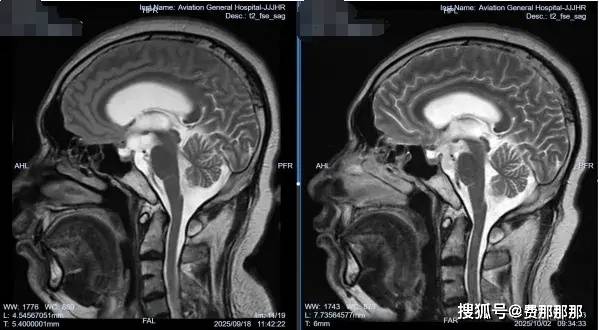

回顾文章开头提到的内蒙古患者图某的情况,他入院后,肖庆教授团队为他做了详细的检查。眼科会诊发现他已有视野缺损和视神经乳突水肿,这表明他的颅内高压已经持续了一段时间,并对视神经造成了损害。他的头颅CT/MR检查显示多发囊性占位,视交叉受压改变,结合他的流行病学史,可以明确脑囊虫病诊断。

术中内镜下可见右侧脑室壁粗糙,广泛炎性黄白色突起肉芽增生——这是既往有过颅内感染的典型表现。肖庆教授更加坚定了之前的判断,进行第三脑室底造瘘,并在基底池内取出数枚囊虫占位,大者外观达2*2cm;同时探查发现基底池内部有多发黄色网状粘连,基底动脉搏动差。